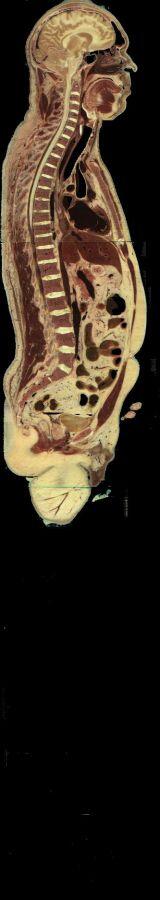

Un homme et une femme ont donné leur corps à la science et accepté d'être découpés après leur mort (l'homme était un condamné à mort américain....).

Les coupes anatomiques réalisées tous les millimètres pour l'homme, tous les 1/3 de millimètre pour la femme ont été numérisées et tout internaute peut appeler n'importe quelle coupe (axiale, coronale ou saggitale).

Bien évidemment, on n'a pas fait trois coupes (question pratique qui vient tout de suite à l'esprit des élèves !) mais une seule, axiale. Les coupes coronales et parasagittales ont été obtenues par reconstitution (d'où la présence parfois de bandes ou de décalages).

Coupes anatomiques d'un homme ou d'une femme

Vous pourrez choisir entre homme et femme et entre tête et corps entier.